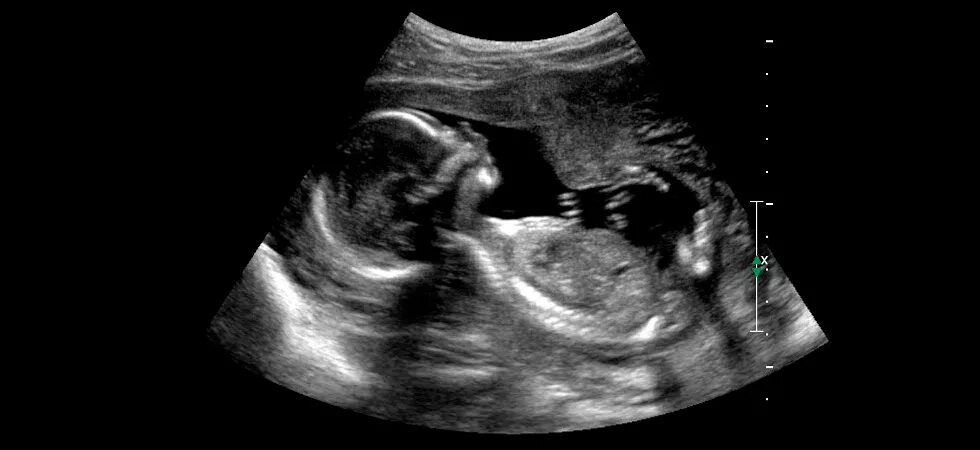

18 недель как выглядит малыш